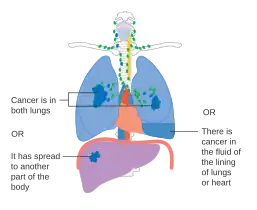

- Diagrams of main features of staging

-

Stage IA and IB lung cancer -

Stage IIA lung cancer -

Stage IIB lung cancer -

One option for stage IIB lung cancer, with T2b; but if tumor is within 2 cm of the carina, this is stage 3 -

Stage IIIA lung cancer -

Stage IIIA lung cancer, if there is one feature from the list on each side -

Stage IIIB lung cancer -

Stage IV lung cancer